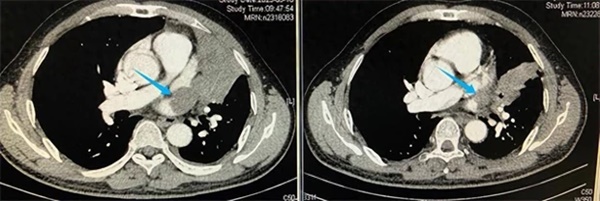

Theo yêu cầu của bác sĩ tại một bệnh viện địa phương, bác đã tiến hành chụp CT và nội soi phế quản. Báo cáo cho thấy một khối u rất lớn ở nửa phổi trên bên phải và đã "nuốt chửng" một phần tim.

Khối u của bác Ngụy thu hẹp đáng kể sau 4 tuần tiến hành hóa trị

Mặc dù sau 4 tuần tiến hành hóa trị, kích thước khối u đã thu nhỏ nhưng việc cắt bỏ vẫn tiềm ẩn khá nhiều rủi ro đe dọa tính mạng. May mắn với kinh nghiệm dày dặn, các y bác sĩ tại Bệnh viện Phúc Kiến đã thành công loại bỏ khối u.